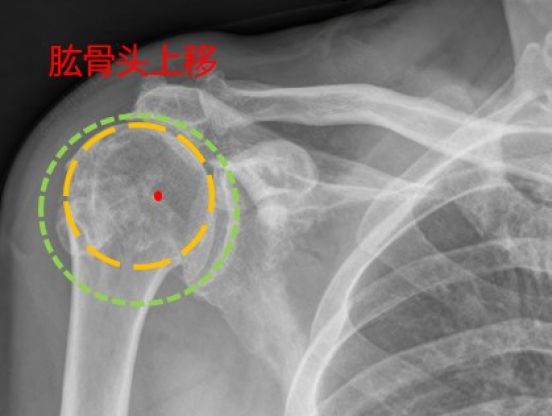

• 反肩置换术:高龄肩袖撕裂伴假瘫的“治疗新径”

丁少华

宁波市医疗中心李惠利医院